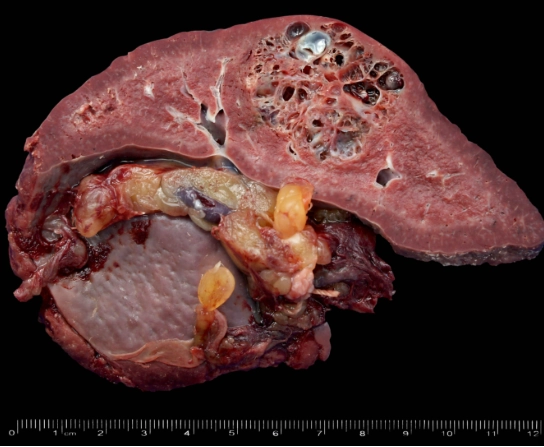

• U mạch máu ác tính lách (Splenic angiosarcoma)